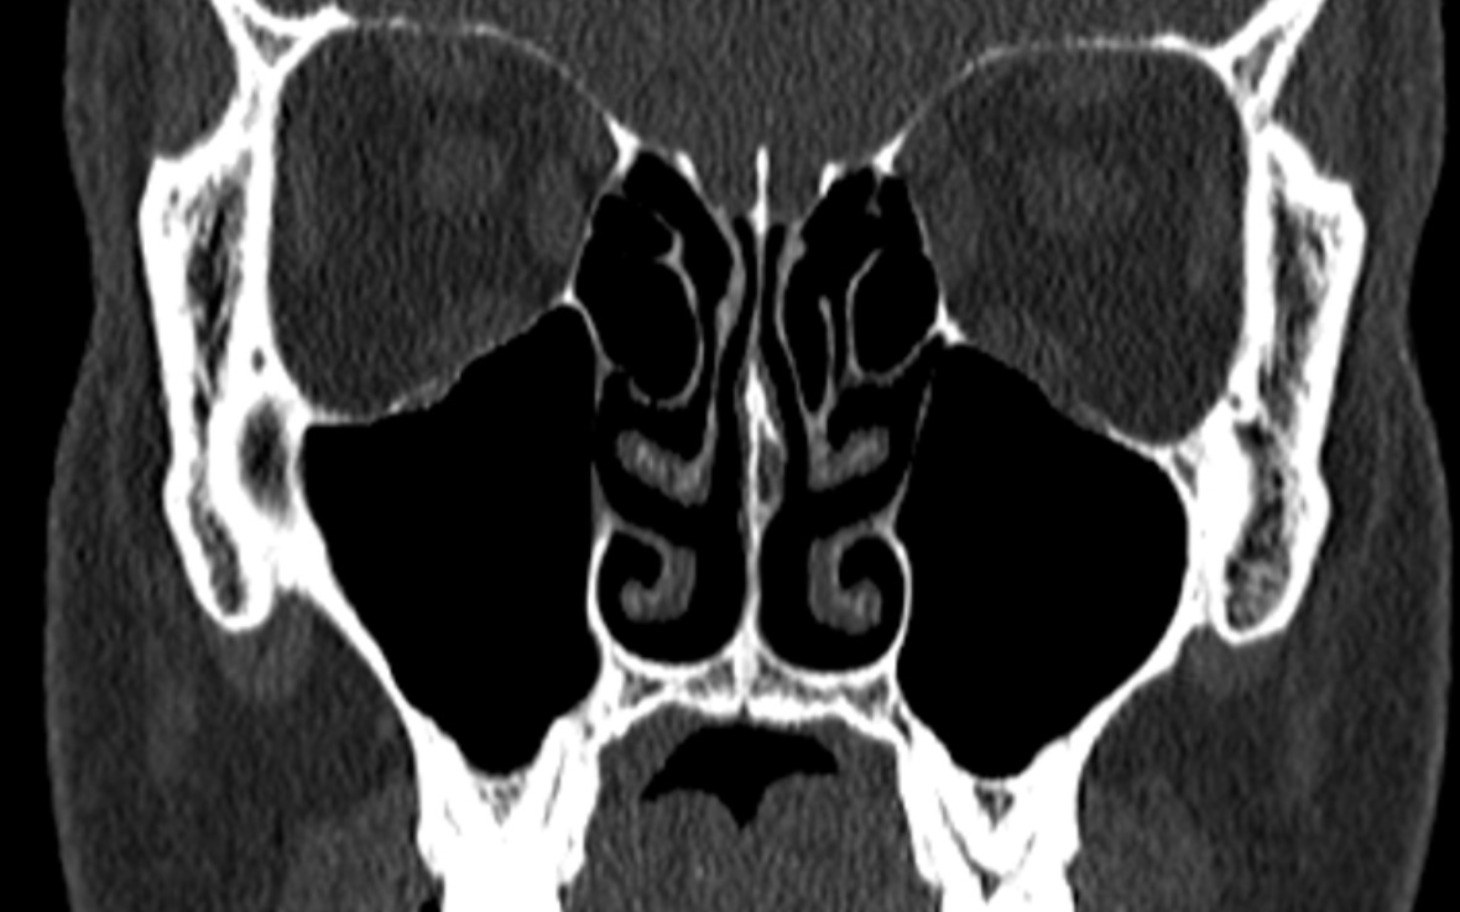

Zabieg ten polega na przecięciu mikrowłókien nerwowych, odpowiedzialnych za stymulację błony śluzowej nosa i uczucie ciągłego zatkania.

Przez długi czas chodziłem od lekarza do lekarza, szukając pomocy u różnych laryngologów, ale niestety nikt nie potrafił skutecznie rozwiązać mojego problemu z ciągle zatkanym nosem, przez co nabawiłem się bezdechu sennego. W końcu podczas prywatnej konsultacji dowiedziałem się o nowoczesnym zabiegu, który może mi pomóc, ale niestety nie jest on refundowany przez NFZ i dostępny jedynie prywatnie.